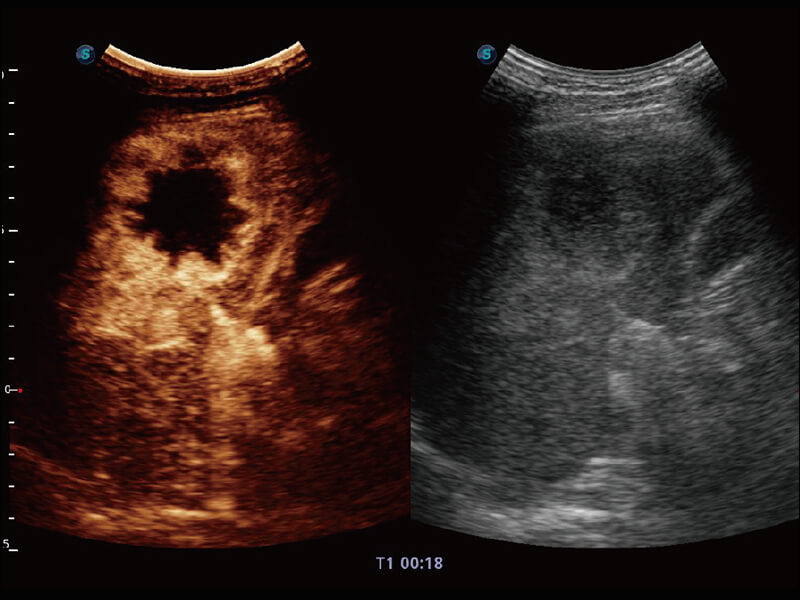

超宽频带技术,为容积成像带来优质的二维图像基础,为您呈现丰富的结构细节,栩栩如生地展示宝宝的宫内形态以及各种组织的立体结构。